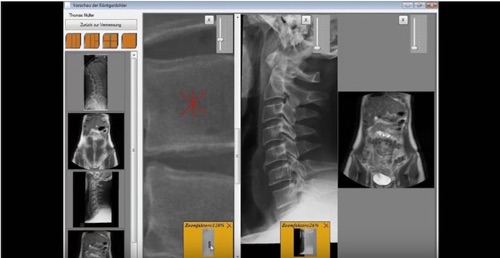

HWS Vermessung lat und a p

Nach der Vermessung folgt die Behandlung. Um alle notwendigen Messergebnisse übersichtlich dargestellt zu bekommen, können Sie den Betrachtungsassistenten starten. Dort können Sie ein bis vier Röntgenbilder übersichtlich anzeigen lassen und je nach technischer Ausstattung auch auf einem Behandlungsmonitor abbilden. Die Vergrößerungsfunktion steht Ihnen natürlich auch hier zur Verfügung. Erstmals können Sie CT und MRT Aufnahmen in einer Anwendung visualisieren.